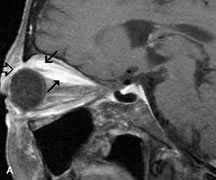

Intraorbital and intracranial optic nerve sheath meningiomas are usually isointense to cortical gray matter on Tl-weighted images and remain isointense on proton density studies (Fig. 15). Gd-DTPA is useful in delineating the intracranial extension of optic nerve meningiomas.7,47 The hyperostosis of bone and calcification associated with meningiomas are not demonstrated as well on MRI studies as on CT scans.20,37 Gd-DTPA–enhanced MRI also appears promising in the study of the permeability of the blood–brain barrier in selected optic neuropathies.22,48 MRI may reveal an enlarged optic nerve and some degree of contrast enhancement in cases of optic neuritis.49

Fig. 15. A. T1- and (B) T2-weighted MR scans demonstrate a mass causing fusiform enlargement of the optic nerve sheath complex. The peripheral portion of the mass, representing the meningioma, is isointense to brain on the T1-weighted scan and notably hypointense on the T2-weighted scan. The central portion of the mass, representing an edematous optic nerve, is very hyperintense on the T2-weighted scan (arrow), C and D. Postcontra fat-suppressed T1-weighted scans demonstrate intense peripheral enhancement of the meningioma surrounding the central nonenhancing optic nerve (arrow). Also note the enhancing Intracranial “dural tail” (double arrow).